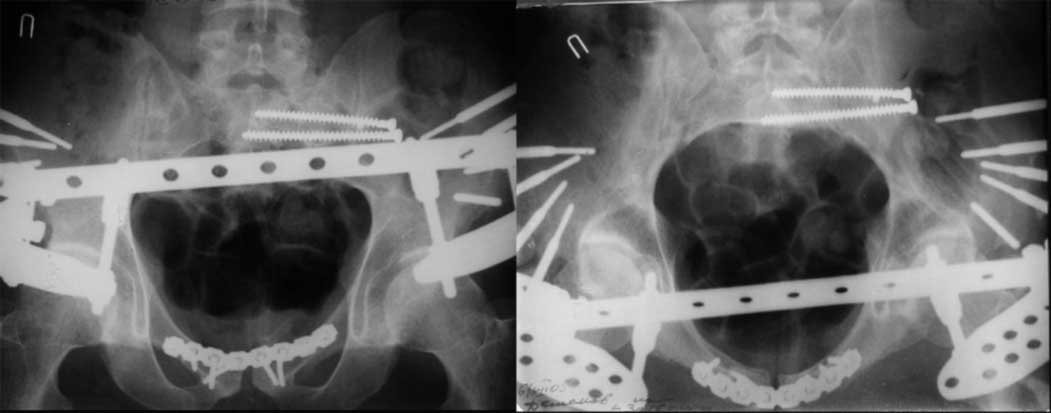

23.09.2003. Одновременный остеосинтез переднего и заднего тазовых полуколец

и 8месяцев после операции

Это наблюдение 5-летней давности тогда кровопотеря составила 2,5 литра. В настоящий момент мы теряем не более 0,7-1,5 литров при одностороннем повреждении и около 2,5-3 литров тогда, когда речь идет о двусторонних повреждениях. Клинический пример.